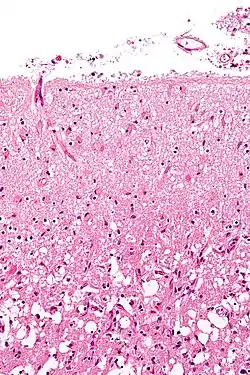

Micrograph showing cortical pseudolaminar necrosis, a finding seen in strokes on medical imaging and at autopsy. H&E-LFB stain.

Micrograph of the superficial cerebral cortex showing neuron loss and reactive astrocytes in a person that has had a stroke. H&E-LFB stain.